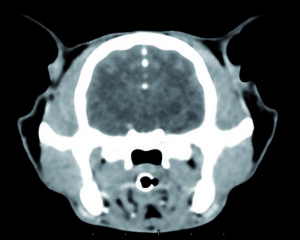

Le donne che sono in eta’ post-menopausa e assumono degli antidepressivi hanno un aumento piccolo – ma statisticamente significativo – del rischio di subire un ictus, secondo quanto suggerisce una ricerca americana.

Dallo studio non e’ chiaro se prendere antidepressivi sia l’unico fattore responsabile dell’aumento del rischio di ictus. Anche la depressione in se’ e’ un noto fattore di rischio di problemi cardiovascolari. I ricercatori hanno cercato di tenere conto di questo elemento nella loro analisi ma non escludono che abbia influenzato i risultati finali. Quanto al tipo di antidepressivi usati, lo studio non ha rilevato differenze nel rischio di ictus tra due grandi classi di farmaci, i cosiddetti inibitori selettivi del reuptake della serotonina (SSRI) o gli antidepressivi triciclici (TCA), anche se i primi sembrano comportare un maggior rischio di ictus emorragico causato da sanguinamento nel cervello. La coordinatrice della ricerca, dottoressa Sylvia Wassertheil-Smoller dell’Albert Einstein College of Medicine, sottolinea che curare la depressione e’ importante e che le donne non devono smettere di prendere i farmaci prescritti senza prima consultare lo psichiatra. Piuttosto, secondo la ricercatrice, vanno soppesati rischi e benefici: questi ultimi possono comunque restare rilevanti, rispetto al piccolo aumento del rischio di ictus rilevato dallo studio. Nuove ricerche, intanto, cercheranno di approfondire il legame tra farmaci antidepressivi e rischio di ictus, soprattutto dopo la menopausa.